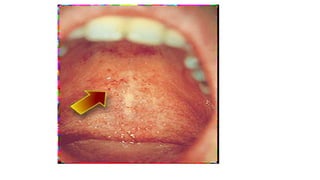

Koplik spots

Koplik spots are grayish white dots, usually as small

as grains of sand, that have slight, reddish areolae;

occasionally they are hemorrhagic.

Tend to occur opposite the lower molars but may

spread irregularly over the rest of the buccal

mucosa.

As they fade, a red, spotty discoloration of the

mucosa may remain.

Koplik Spots, if seen, are Pathognomonic for

Koplik spots Koplik spotsare grayish white dots, usually as small as grains of sand, that have slight, reddish areolae; occasionally they are hemorrhagic. Tend to occur opposite the lower molars but may spread irregularly over the rest of the buccal mucosa. As they fade, a red, spotty discoloration of the mucosa may remain.